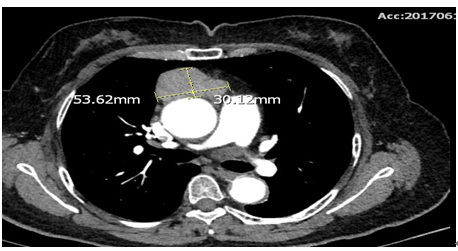

日前,一位56岁女性患者因“颜面部浮肿”就诊于我院心内科,胸部CT检查提示胸腺瘤(图4)转入胸外科,通过“经剑突下胸腔镜全胸腺切除术”,患者恢复良好已出院。

图4